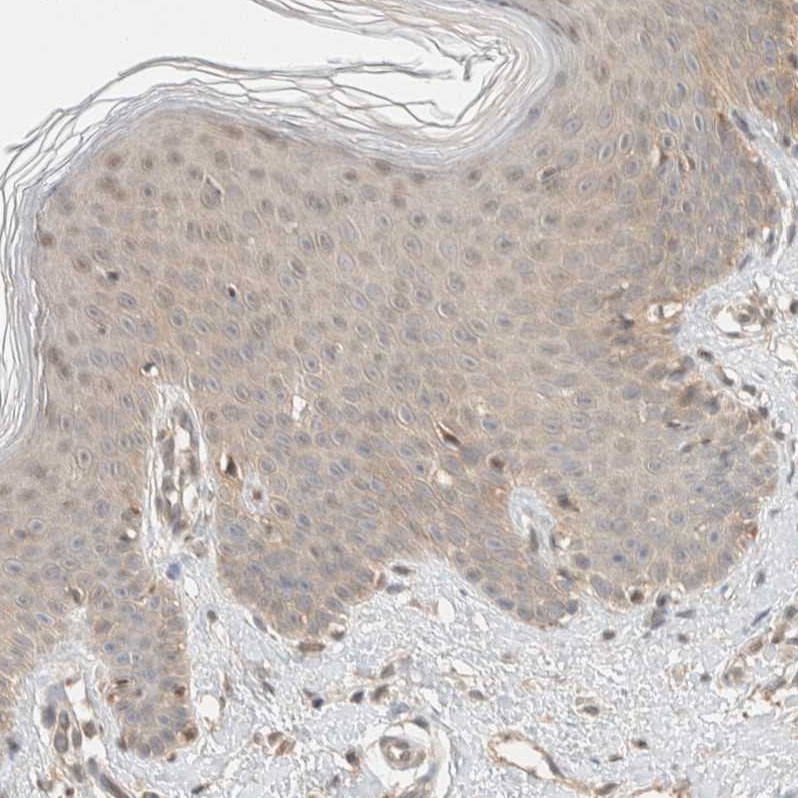

Immunohistochemical staining of human placenta shows moderate nuclear and cytoplasmic positivity in trophoblastic cells.